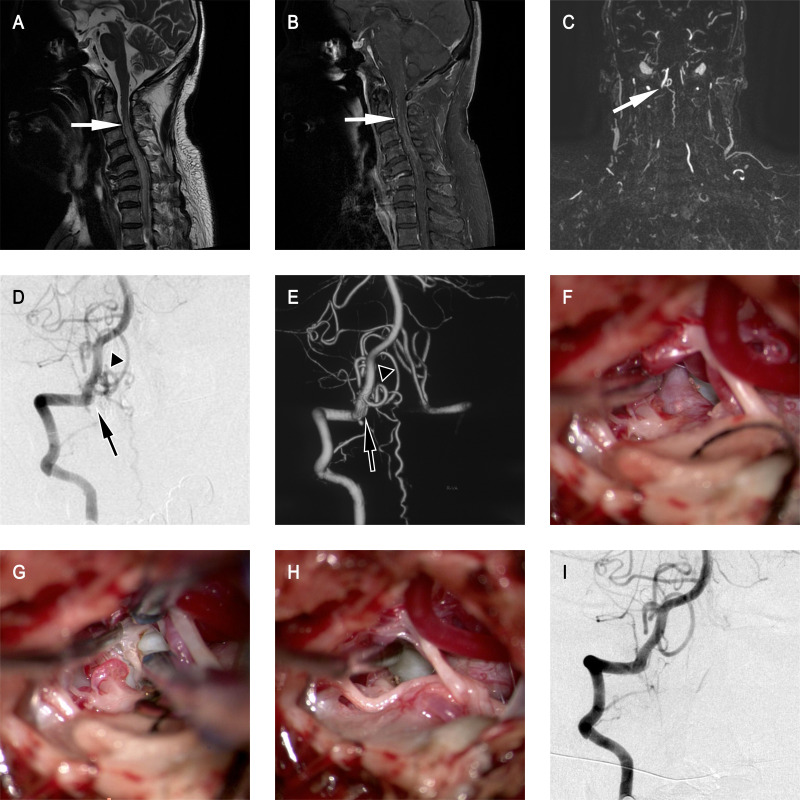

Results: The patients' median age was 56 years (IQR 47-62 years). The majority of patients were men with 166 (83.8%) patients. The most common clinical manifestation was SAH (52.0%), followed by venous hypertensive myelopathy (VHM) (45.5%). The most common CCJ AVFs type was dural AVF, with 132 (63.5%) fistulas. The most frequent fistula location was C-1 (68.7%) and dural branch of vertebral artery (70.2%) was the most involved arterial feeders for fistulas. The most common direction of venous drainage was descending intradural drainage (40.9%), followed by ascending intradural drainage (36.5%). Microsurgery was the most common treatment strategy applied for 151 (76.3%) patients, 15 (7.6%) patients were treated with interventional embolisation only, and 27 (13.6%) received both interventional embolisation and microsurgical treatment. The learning curve for microsurgery only was analysed by cumulative summation method, and the turning point was the 70th case, and blood loss in post-group was lower than that in pre-group (p=0.034). At the last follow-up, there were 155 (78.3%) patients with favourable outcomes (modified Rankin Scale(mRS)<3). Age≥56 (OR 2.038, 95% CI 1.039 to 3.998, p=0.038), VHM as the clinical manifestation (OR 4.102, 95% CI 2.108 to 7.982, p<0.001) and pretreatment mRS≥3 (OR 3.127, 95% CI 1.617 to 6.047, p<0.001) were significantly associated with poor outcomes.

Conclusion: The arterial feeders and direction of the venous drainage were important factors in the clinical presentations. The location of fistula and drainage vein was essential for choosing different treatment strategies. Older age, VHM onset and poor pretreatment functional status predicted poor outcomes.